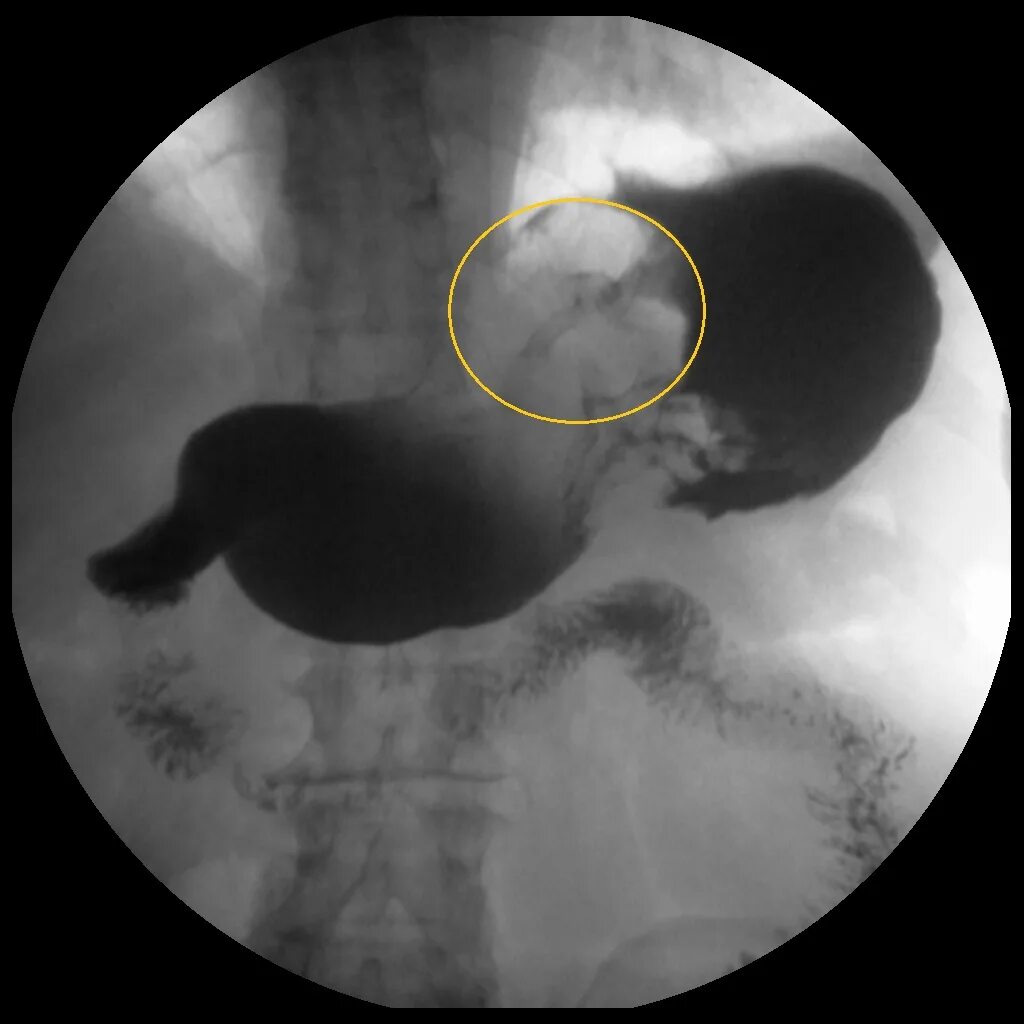

Рентгеноскопия пищевода и желудка с барием

Рентген контрастирование барием. скопия желудка рентген. контрастирование желудка рентген. скопия пищевода рентген.

Рентгенологическое исследование пищевода с бариевой взвесью. рентген исследование желудка с барием. рентгеноскопия желудка с барием. подготовка к рентгеноскопии желудка и пищевода с барием.